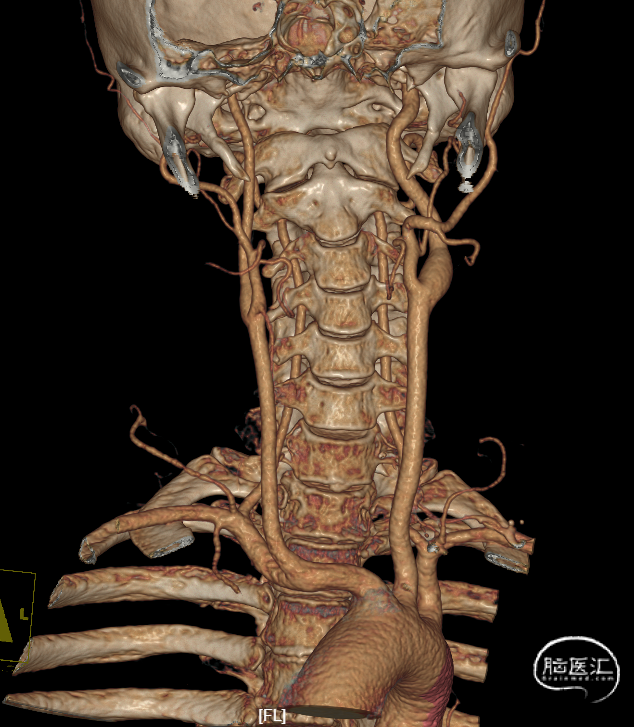

颅内外血管未见明显狭窄。

CT(CTA)检查提示:右颈内动脉C7段大小约3.6×3.8×3.6mm及基底动脉远端动脉瘤形成大小约9.7×7.6×9.3mm。

角度大:

远端弯曲:

血管狭窄:

近端载瘤动脉短: